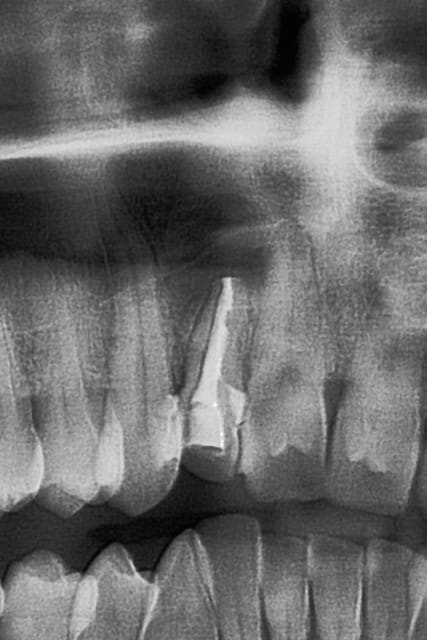

6 mois plus tard...

je vous laisse regarder les images...

la mobilité est redevenue quasi physiologique...

en fait, c'était le but premier de cette intervention...la "régénération osseuse" , car à mon avis et n'en déplaise aux puristes, cette dent est vraisemblablement condamnée à moyen terme

n'en déplaise à tillc...la radio est à un peu plus de 6 mois post op, on en est à 8 mois post op et toujours RAS...

le patient m'a promis de venir faire contrôler çà ce printemps...on verra à ce moment là...